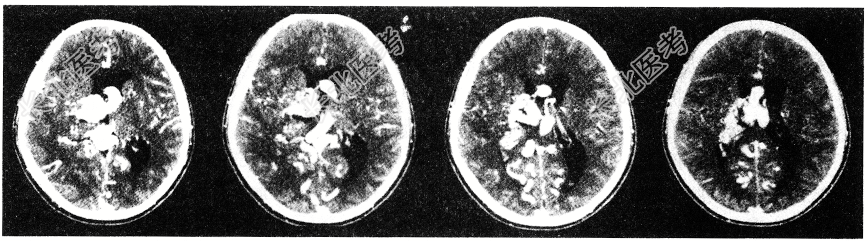

- 单项选择题男性患者,32岁。头痛、癫痫, 查体发现视盘水肿,CT检查如图, 最可能的诊断为

A、钙化灶

B、少突胶质瘤

C、脑囊虫

D、动静脉畸形

E、结节状硬化